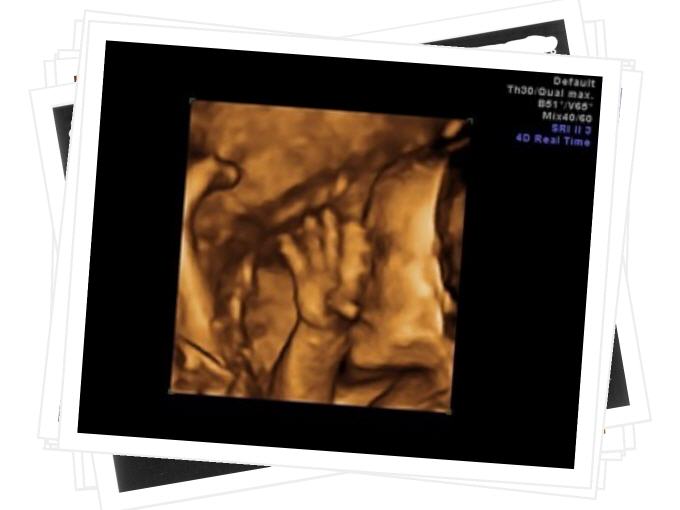

Geburtshilfe

Auf den folgenden Seiten können Sie sich einen Überblick über unser umfassendes Leistungsspektrum im Bereich Geburtshilfen und Pränataldiagnostik verschaffen.